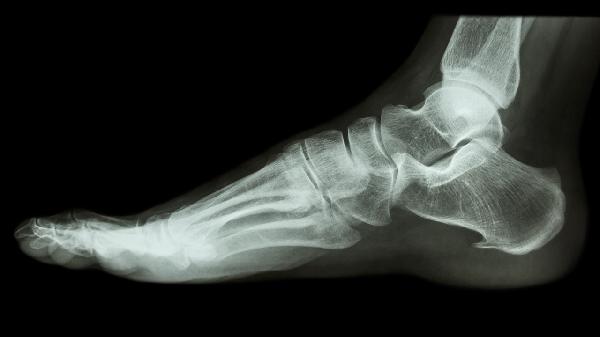

对早期骨关节炎的软骨退化,该药能减缓进程并改善功能,减少骨质增生刺激引发的疼痛。多见于负重关节,活动时有摩擦感。建议联合钙剂补充并控制体重。